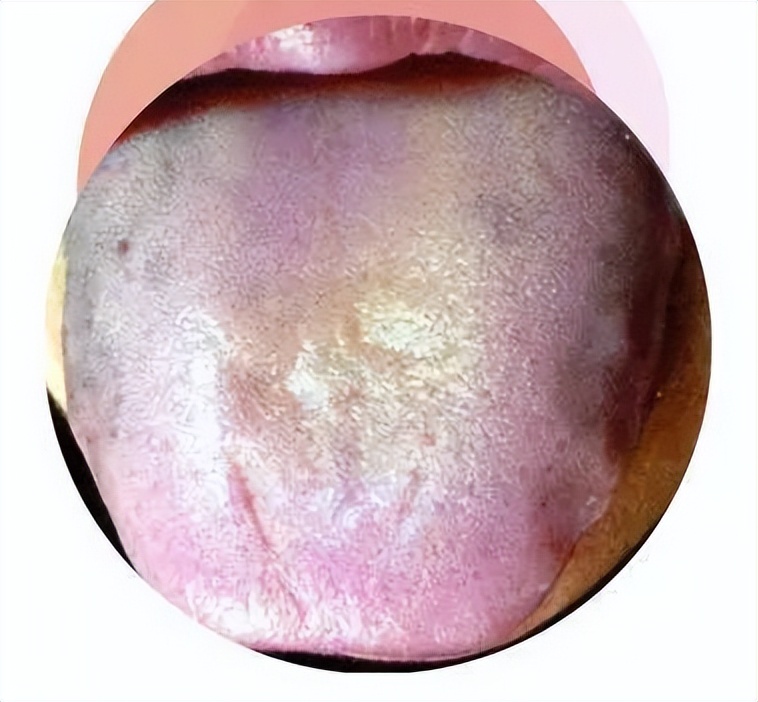

首先看上面的图:

心肺居于上部,故而舌尖主要反映心肺;脾胃处于中部,因此舌中部主要对应脾胃;肾位于下部,所以舌根部主要指代肾;肝胆位于躯体两侧,故而舌边主要代表肝胆,左边属肝,右边属胆。此种说法多应用于内伤杂病。2. 依三焦位置之上下次序来划分诊舌部位,舌尖主要代表上焦,舌中部主要代表中焦,舌根部主要代表下焦。这种分法多见于外感病变。3. 以胃脘来分属诊舌部位,舌尖部主要代表上脘,舌中部主要代表中脘,舌根部主要代表下脘。以舌之各部位对应脏腑,此乃当前研究生物全息律的课题之一,虽说法众多,但皆具参考价值,于临床诊断上,可结合舌质舌苔之诊察予以验证,然必需四诊合参,综合判断,不可过度机械死板。